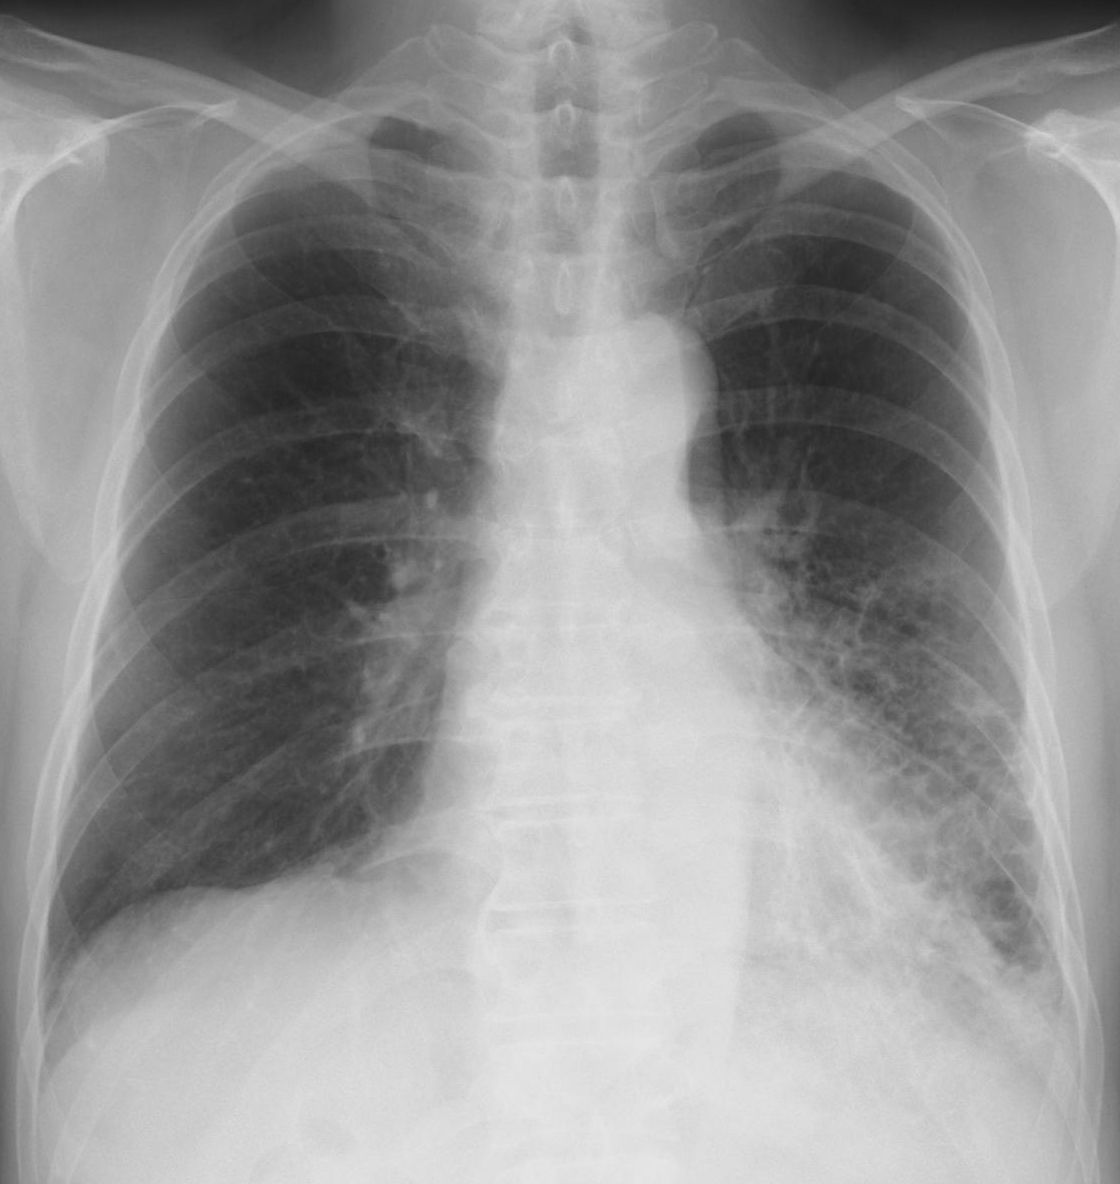

D.肺気腫(透過性亢進・過膨張) ①肋骨の陰影が薄く線量過多もしくは骨量の減少を示唆。

②胸郭全体が樽のように過膨張。

③横隔膜が第12肋骨の部位にあり同時に濃淡に差があり横隔膜後部の肺野が含気過多になっている。また左横隔膜中1/3が不鮮明、平低化(ド-ム状になっていない)。

④左右とも上肺野の肺紋理(肺の血管影・気管支影)が消失して追うことができない。

⑤左右下肺野には小粒状影・線状影をみとめ心辺縁がはっきりしない(シルエットサイン陽性)。

⑥右横隔膜化に弧状の陰影をみとめる。

[評価] 肺野の透過性(血流減少・含気の増加)が亢進、肺の膨張した肺気腫の所見、同時に骨量の減少があり高齢もしくは骨粗鬆症を示唆する写真になっている。⑥は肝臓の凹凸を反映していると考えるが他の腫瘤性陰影の可能性もあり検索が必要になる。